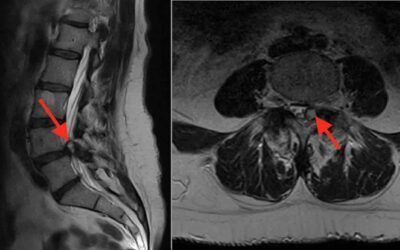

Hernia discal: Síntomas, causas y tratamientos

La hernia discal o hernia de disco es una afección que ocurre cuando el núcleo pulposo del disco intervertebral se desplaza a través del anillo exterior...

Estenosis de canal lumbar: síntomas, causas y tratamiento

La estenosis de canal lumbar es una afección que afecta la columna vertebral y se caracteriza por el estrechamiento del canal vertebral en la región lumbar. Esta guía te proporcionará una comprensión completa de la estenosis de canal lumbar, sus síntomas, causas y opciones de tratamiento